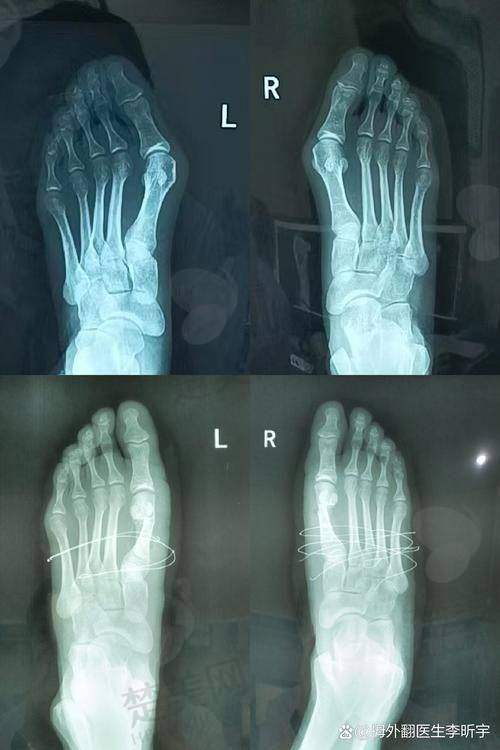

苏医生拿手的是“微孔祛大脚骨”技术,和传统骨科手术比起来,有三大绝活。首先,切口特别小,只有3.5毫米,而传统手术的切口5厘米起步,这差距可太大了。其次,不用打钢钉钢板,靠榫卯结构就能固定骨头,听起来就特别厉害。末尾,术后马上就能走路。我亲眼看到一个姑娘自己走出手术室,这修复速度简直绝了。

咱小区退休的王大爷就是个典型例子。他十年前在国有医院做过传统手术,结果去年复发得更重度了,找到苏敬达医生坐诊的医院时,脚趾都歪成麻花了。苏医生给他做了三维重建后,采用环V型截骨术,现在王大爷天天在紫竹院公园暴走两万步,身体可好了。